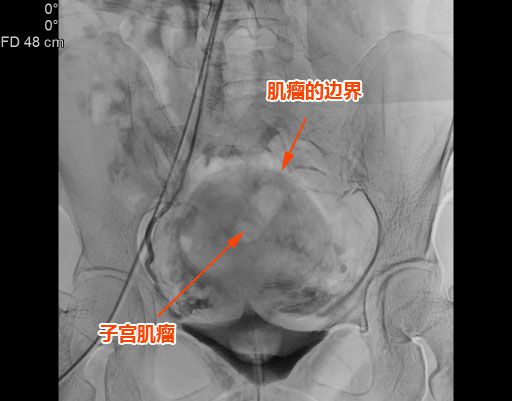

△子宮肌瘤巨大,邊界清晰。

該名患者來自揭西,有下腹痛1個多月,腹部外觀像孕婦,經影像學檢查可見子宮前壁肌間有1個7.5cm左右的巨大肌瘤。此類患者如采用腹腔鏡或傳統手術治療,需要做子宮切除手術。患者因年紀僅40餘歲,相對較輕,想要保住子宮。

随後,李旭丹主任與胡志華主任聯手爲患者實施手術,通過患者股動脈穿刺,置入微導絲、導管,經動脈自然腔道将導管送達左右側髂總動脈進行造影,可見肌瘤供血血管,随後利用微導管将特制栓塞材料送達子宮動脈進行栓塞。造影顯示子宮肌瘤供血已被掐斷,順利完成手術。